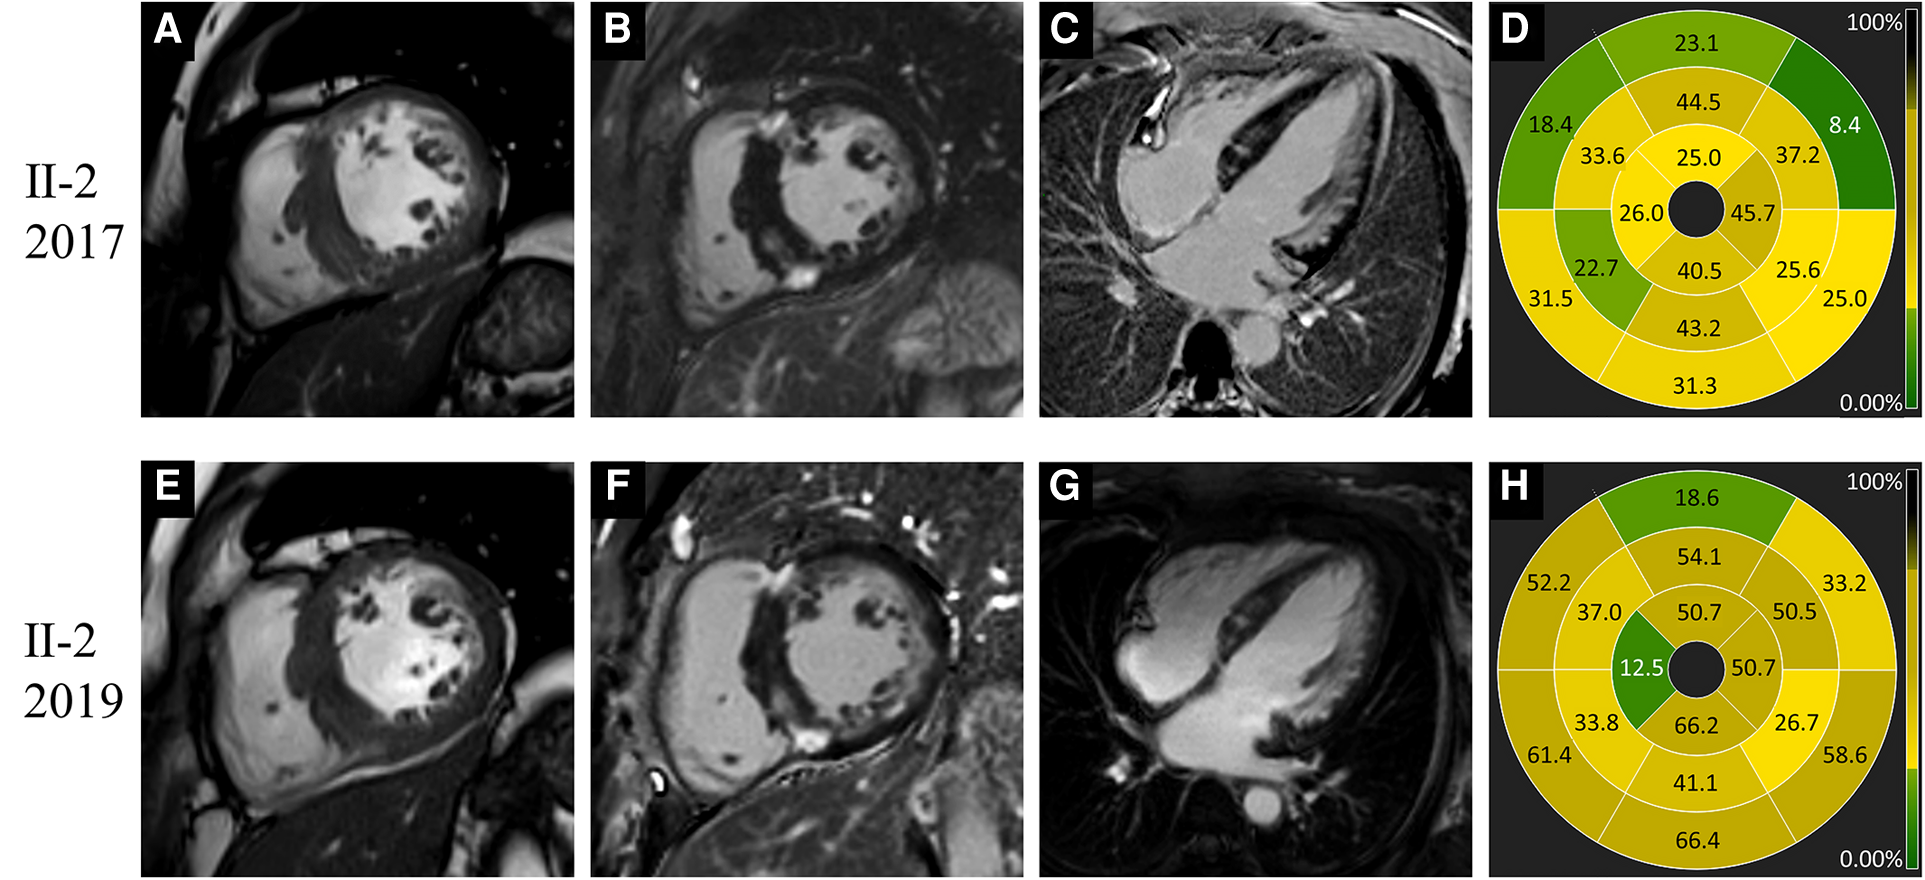

Figure 4

www.frontiersin.org

Figure 4. Images of representative patient with Danon disease (Ⅱ-2, a 44-year-old female). In 2017, cine cardiac image in short-axis view showed increased thickness of intraventricular septum (A). Late gadolinium enhancement predominantly involved the right ventricle insertion points, the left ventricle free wall and intraventricular septum (B–D). In 2019, the change of cardiac structure was slight on cine image (E). The extent of late gadolinium enhancement (F–H) showed mild to moderate progression compared to 2017.

None of the five female patients (Ⅱ-2, Ⅱ-3, Ⅲ-2, Ⅲ-4, and Ⅲ-5) exhibited substantial symptom deterioration. With regard to Ⅱ-2, the extent and proportion of LGE markedly increased, the LV wall slightly thickened, and the LVEF mildly decreased in 2019 (Figure 4).